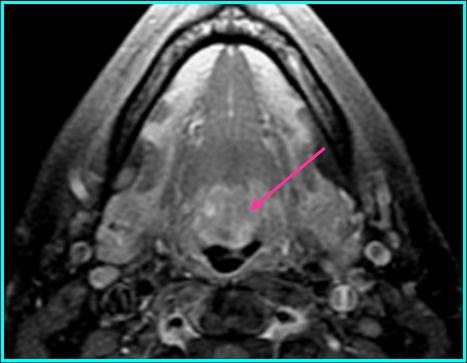

Radiologic Findings

- On MR: high signal with T1 and T2 when compared to muscle; enhancement on T1 post-contrast